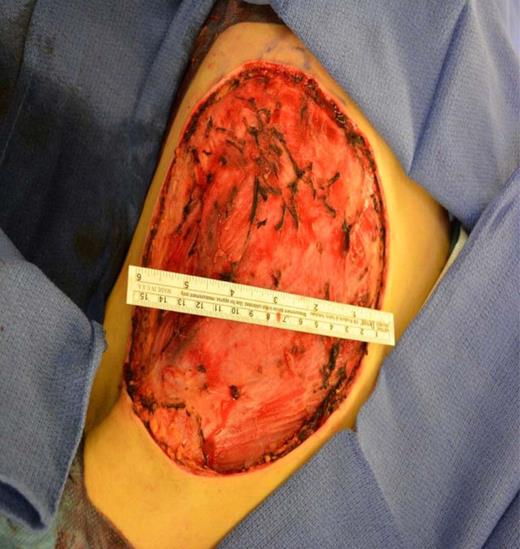

A left mastectomy was performed. The excised mass was 20 × 20 × 25 cm in size (Fig. 3). The tumor did not appear grossly to be invading the chest wall. The pectoralis fascia was free of tumor invasion (Fig. 4). The left chest wall defect was covered temporarily with dual layers dermal regeneration template consists of thin outer layer of silicone and thick inner matrix layer of pure bovine collagen and glycosaminoglycan (INTEGRA®) in the same operation, and subsequently replaced with split thickness skin graft 5 weeks later (Fig. 5). Final histological examination was consistent with phyllodes tumor with low-grade malignant features with negative margins (Fig. 6).

Coverage of the left chest wall defect with a split thickness skin graft.